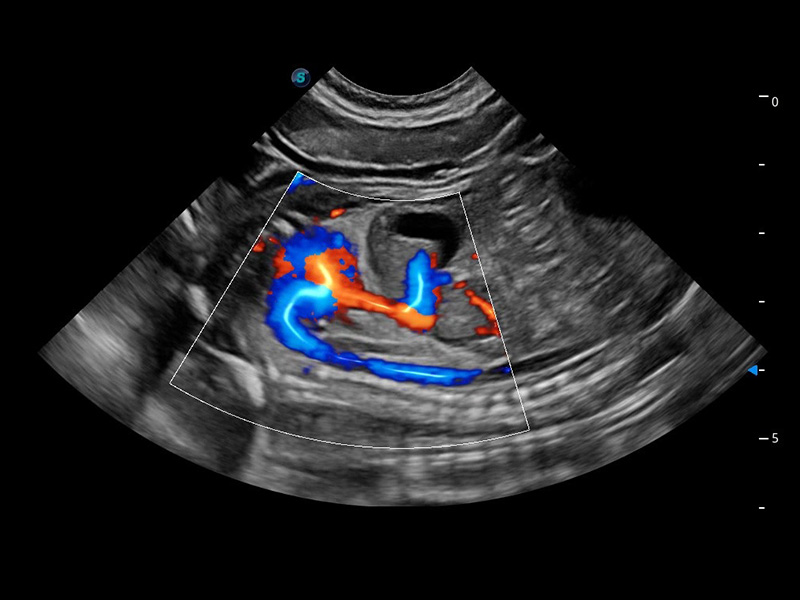

ProPet 60 作为一款高端台式动物超声设备,为动物医生的日常诊断提供了一系列贴合动物临床需求、解决临床实际问题的高级成像功能。凭借全系列高清探头,满足医生对腹部、心脏、生殖、浅表、肌骨等成像的所有需求,切实帮助您提升检查效率,提高诊断信心。

兽用彩色多普勒超声诊断系统

动物是人类最亲密的朋友和最值得信赖的伙伴。16877太阳集团也一直致力于探索动物专用的超声影像解决方案。 全新推出的ProPet系列,是16877太阳集团在动物超声影像智能化、专业化、精准化的一次跨越式革新。动物不能用言语来表述自己的不适,通过超声影像,ProPet系列搭建了动物医生与不同物种沟通的“桥梁”,为动物医生注入了“治愈之力”。